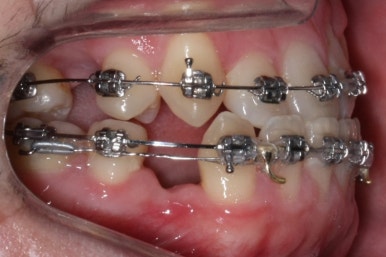

위아랫니가 각각 가지런해지고 있는 것을 볼 수 있습니다.

적절한 시기가 되면 악궁확장장치를 제거하고, 확장장치가 걸려있던 치아도 가지런하게 해줍니다.

윗니는 아직 가지런하게 하는 작업 중이며, 아랫니는 가지런하게 하는 작업은 거의 다 되었습니다.

이제 아랫니는 이 뽑은 자리를 앞뒤로 당겨서 없애주어야 합니다. 보통은 앞니가 뒤로 많이 들어오기 때문에 이번 환자분 처럼 앞니가 거꾸로 물리는 경우 앞니를 제대로 물리게 해줄 수 있습니다.

계속 윗니는 가지런히 해주고 있으며 아랫니는 앞뒤를 뒤로 당기고 있습니다.

거꾸로 물리던 앞니가 서서히 개선되어 가는 것을 볼 수 있습니다.